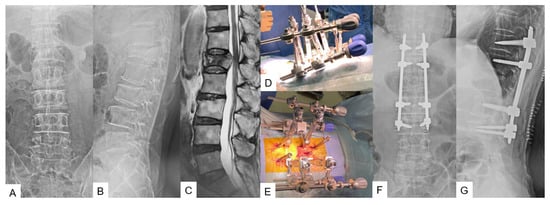

3.2.1. Adult Spinal Deformity [12]